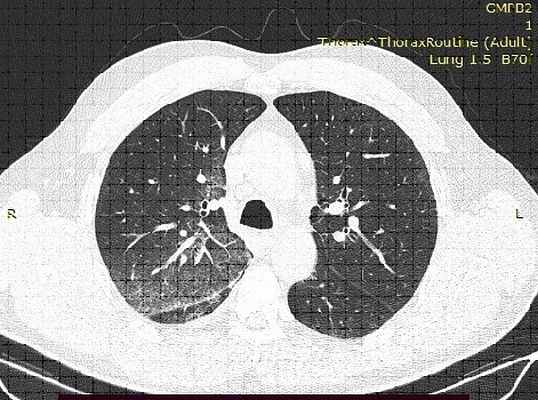

КТ-картина имбибиции верхней доли правого легкого

Золотым стандартом в диагностике легочного кровотечения является выполнение компьютерной томографии с внутренним контрастированием (Ангио-КТ), позволяющее как оценить состояние легочной паренхимы, так и определить локализацию субстрата для кровотечения, а также выявить патологические бронхиальные артерии, диагностировать аномалии и пороки развития легких и их сосудов. Одной из важнейших задач при выполнении Ангио-КТ является оценка проходимости ветвей легочной артерии, поскольку нередко легочное кровотечение является следствием развития ТЭЛА, и подходы к лечению таких пациентов принципиально отличаются. В тоже время, противопоказаний к выполнению экстренной Анго-КТ немного, и для их выявления, порой, достаточно подробного сбора анамнеза и выполнения биохимического анализа крови.

Рис. 2. МСКТ у женщины 60 лет с рецидивирующим КХ вследствие бронхоэктазов средней доли справа: определяется дилатация и выраженная извитость бронхиальных артерий (показано стрелками), вазодилатация больше выражена в легочной паренхиме.

Компьютерная томография позволяет визуализировать изменения в легких, которые не видны при проведении рентгенографии грудной клетки (например, бронхоэктазы, аспергиллома или новообразования небольших размеров)

[18]. КТ-признаками состоявшегося легочного кровотечения могут быть инфильтративные изменения в паренхиме легких в виде участков “матового стекла” или консолидации, а также развитие ателектаза сегмента или доли легкого вследствие закупорки бронха сгустком крови [18, 19].

Установить локализацию кровотечения из бронхиальных артерий можно при помощи мультиспиральной КТ (МСКТ) с контрастированием, кроме того, данный метод позволяет выявить аномалии в системе легочного кровообращения 22. МСКТ-ангиография обеспечивает лучшую визуализацию бронхиальных и системных небронхиальных артерий (рис. 2) по сравнению с обычной ангиографией [23]. За исключением жизнеугрожающих состояний, проведение КТ рекомендовано перед бронхоскопией. Противопоказания к МСКТ-ангиографии в основном относительные - нарушения системы гемостаза, тяжелая почечная недостаточность, аневризма аорты, аллергия к йодсодержащим препаратам.